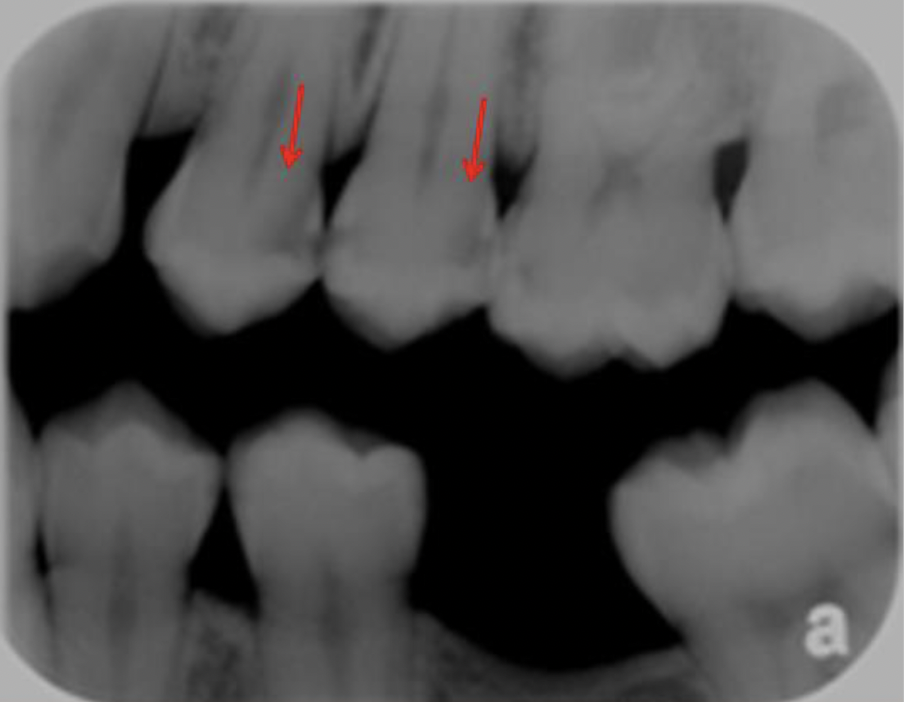

Phenomenon in which the dentin artifact simulates caries; the lesion is outlined by normal anatomic structures and it is a RELATIVE radiolucency

Interproximal "burnout"

What is going on in the following radiograph?

Interproximal burnout

69